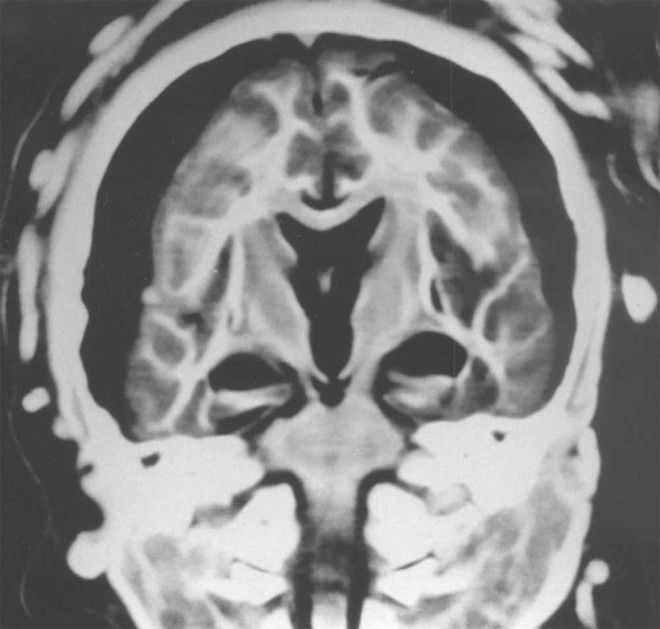

5. Рентген мозга 6-летней девочки показал, что в нее попала молния. Здесь показаны ее орбиты с глазами, зрительными нервами (стрелки) и зрительными мышцами.

6. Рентген мозга 15-летней девочки показывает, что между белым и серым веществом мозга есть разделение. Стрелки указывают на воздух, окружающих мозг.

7. А этот рентген показал, что мозг 5-летнего мальчика сохранился в идеальном состоянии.